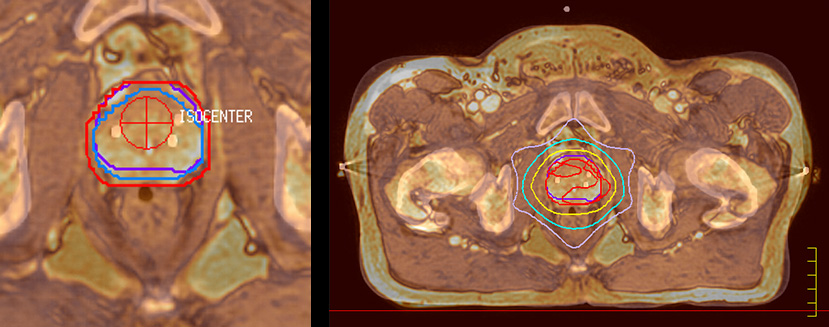

“We currently use MR-RT mainly in the abdomen and pelvis region: prostate, colorectal, pancreatic, cervical, and liver. Also in the brain, we are starting to use it,” says Dr. Yan.

“The biggest problem for CT-based planning, especially in prostate, is you can’t see the cancer very well,” says Dr. Stevens. “On CT it can be quite challenging to see the edge of the prostate especially at the apex. When the edge of the prostate can’t be delineated well on CT, radiation oncologists will increase their margins a little bit so they don’t miss it, but that can also increase toxicity.”

“Using MR, the prostate is well delineated. We quickly see the edges of cancerous tumors like in prostate cancer, and as normal structures can be defined, we can optimize the treatment plan to protect these organs and their normal function. This can potentially improve the outcome. And it improves workflow as well. We can contour more quickly, confident that the tumor is going to be in the field.”

“When a patient registers, first CT simulation and MR simulation are done, followed by CT-MR registration on Pinnacle3. Then the target and normal organ delineation is performed on MR images. Meanwhile we create a reference CT image for online treatment and localization correction. During the treatment phase we can perform additional MRI scans to visualize the anatomy changes and create an adaptive plan. This plan basically adapts the treatment plan to the changes.”